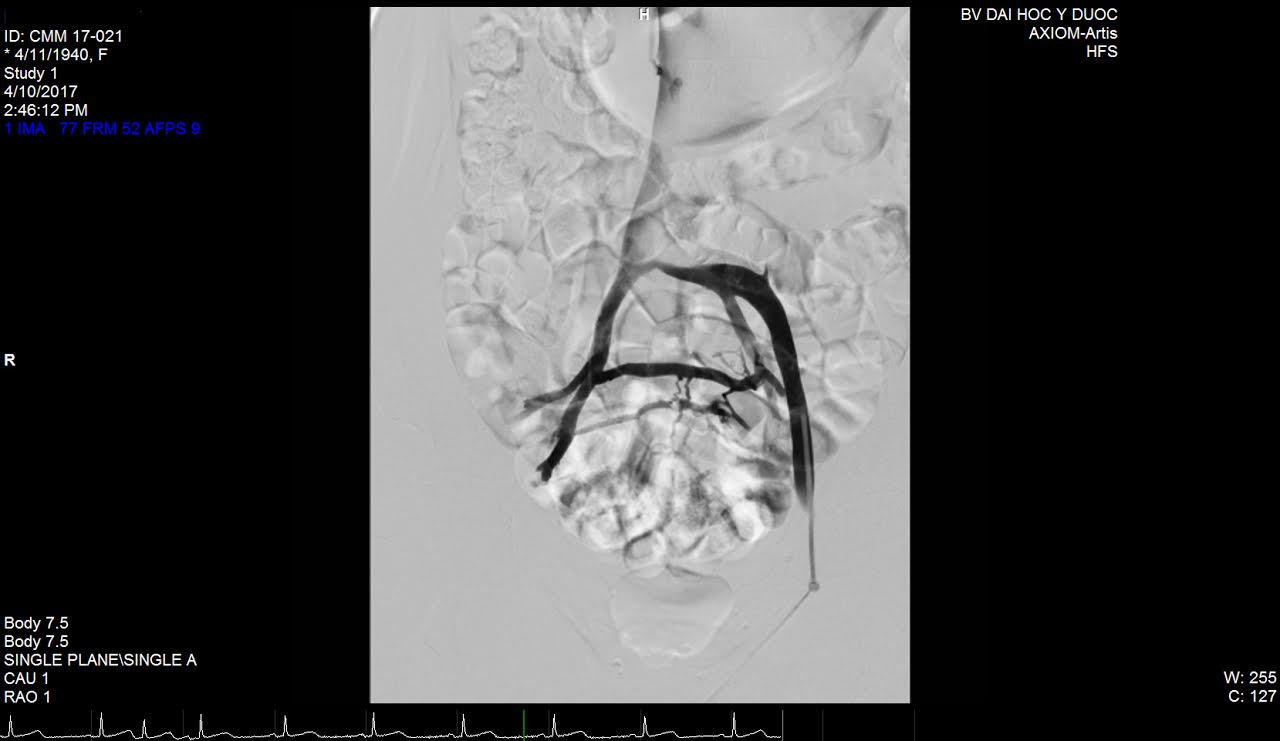

![]() |

| Tĩnh mạch được thông sau khi được can thiệp nội mạch thành công (ảnh Bệnh viện Đại học Y dược TP Hồ Chí Minh cung cấp) |

Phương pháp điều trị được thực hiện bằng cách nong bóng và đặt giá đỡ tĩnh mạch (stent) chỉ qua một vết đâm kim ở vùng bẹn đùi. Sau mổ vài tiếng đồng hồ, người bệnh có thể đi lại và có thể xuất viện cùng ngày.

Qua đánh giá, các bệnh nhân bị suy tĩnh mạch chậu trái được điều trị theo phương pháp này cho thấy hiệu quả rõ rệt, chất lượng cuộc sống của người bệnh cải thiện đáng kể và ổn định.